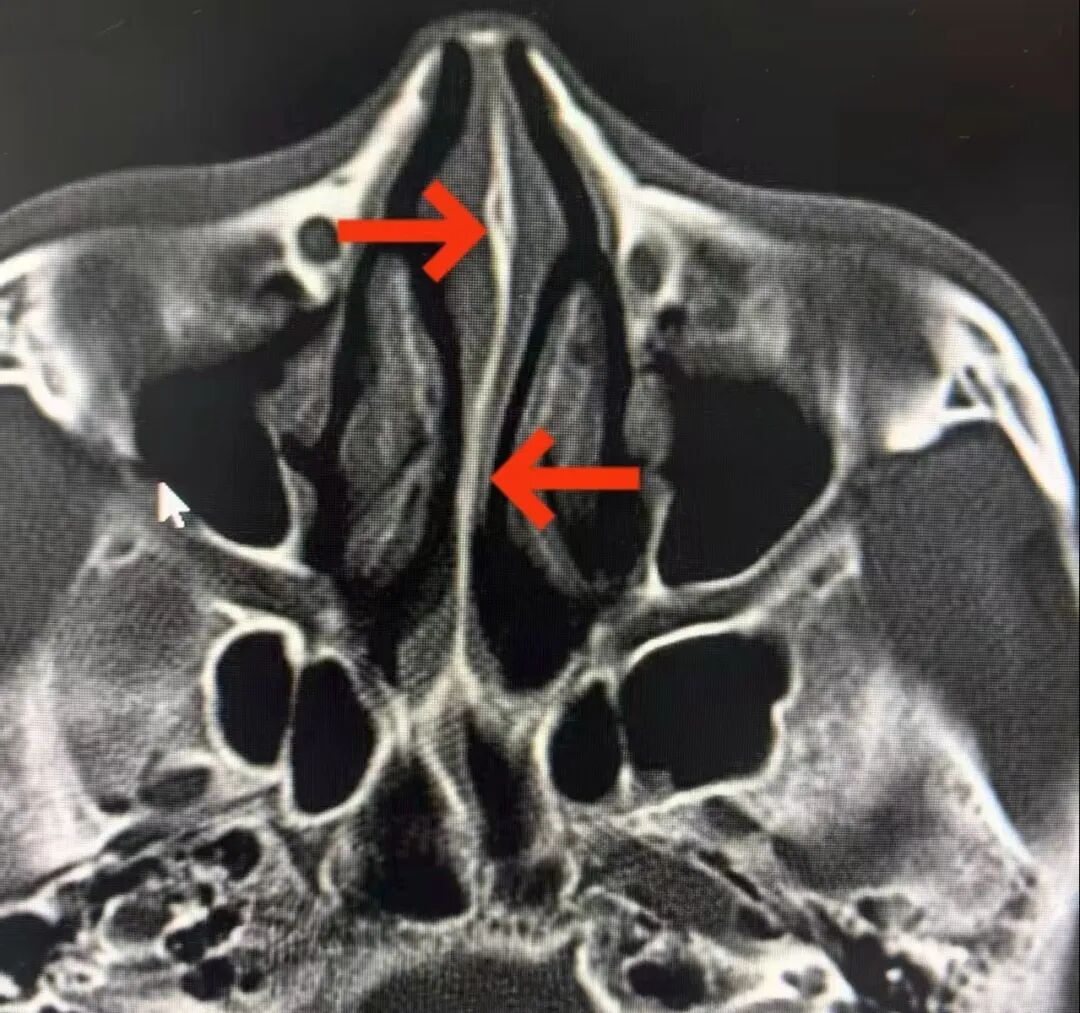

37岁的文先生长期受左侧头痛折磨,转辗多家医院检查均未发现异常,常规治疗也收效甚微。因头疼再次剧烈发作来诊,杨主任接诊后仔细询问病情,检查发现文先生的鼻中隔呈“S”型偏曲,突出部位恰好压迫到同侧下鼻甲与中鼻甲,结合其头痛的部位、性质与诱发因素,判断其头痛正是由鼻中隔偏曲引起的反射性头痛。

“鼻中隔偏曲不仅会导致鼻塞、鼻出血,当偏曲的突出部位压迫同侧鼻甲时,就会引起同侧反射性头痛,这类头痛常被误诊为神经性头痛或偏头痛。”杨主任解释道。